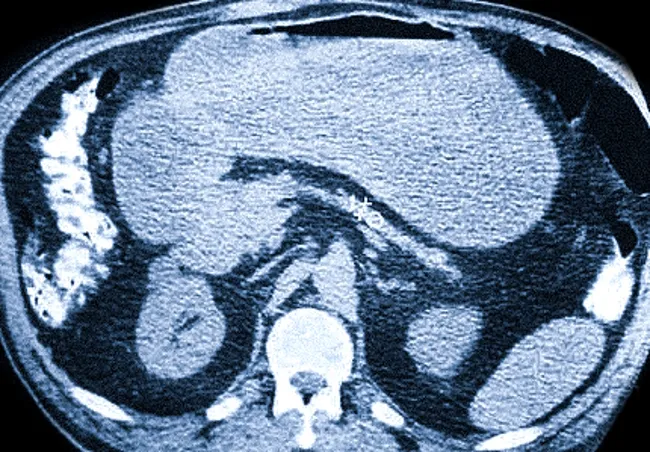

Признаки инволютивных изменений поджелудочной на КТ

Сокращение размеров органа (стрелки) на фоне дистрофических процессов

Затяжные патологические процессы в поджелудочной железе, особенно без должного лечения и коррекции образа жизни, приводят к инволютивным изменениям. Уменьшение органа в размерах, вызванное склерозом или фиброзом, сопровождается потерей его функций и может привести к прогрессированию сахарного диабета и панкреатита с недостаточностью экзокринной и эндокринной функций. На компьютерной томографии это проявляется снижением степени четкости изображения и неоднородной структурой.

У большинства пожилых людей инволютивные изменения затрагивают не только сам орган, но и его протоки. Исследования демонстрируют, что с возрастом объем железы уменьшается. На КТ можно обнаружить признаки стеатоза и хронического панкреатита. В связи с этом риск развития сахарного диабета у данной группы возрастает.

Явная атрофия поджелудочной железы на фоне диабета — орган визуализируется как тонкая линия, рядом с которой может быть обнаружена опухоль антрального отдела желудка.